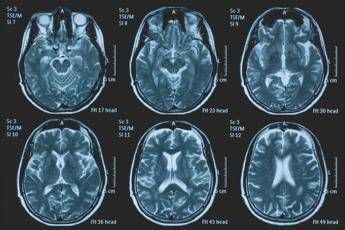

(Adnkronos) – La Commissione europea (Ce) ha autorizzato la commercializzazione condizionata di tovorafenib come monoterapia per il trattamento dei pazienti di età pari o superiore a 6 mesi con glioma pediatrico di basso grado che presentano una fusione o un riarrangiamento del gene Braf o una mutazione Braf-V600, in progressione di malattia dopo una o più terapie sistemiche precedenti. Lo annuncia Ipsen, in una nota, precisando che si tratta della “prima terapia mirata” per questa patologia e che la decisione della Ce si riferisce ai 27 Stati membri della Ue, oltre a Islanda, Liechtenstein e Norvegia. Ogni anno in Ue vengono diagnosticati più di 800 nuovi casi di glioma pediatrico di basso grado (pLgg) con alterazione di Braf.

Questo tumore cerebrale, nonostante sia classificato di basso grado (a lenta progressione), comporta un carico significativo e permanente che accompagna la persona per tutta la vita, causando spesso importanti compromissioni fisiche e neurologiche, tra cui perdita della vista, difficoltà di linguaggio e disfunzioni motorie, che possono incidere in modo significativo sull’istruzione, l’autonomia e la qualità di vita a lungo termine del bambino. Finora, molti bambini con pLgg hanno dovuto sottoporsi a interventi chirurgici invasivi, a più cicli di chemioterapia e a radioterapia, con conseguenti complicazioni della salute.